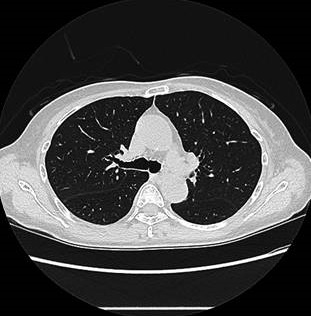

筆者がこれまで遭遇した症例には、肺転移が先に見つかり、全身の原発巣を調べた結果、甲状腺微小乳頭癌にたどり着いたものが数例あります(浸潤型微小乳頭癌)。

また、頚部リンパ節転移が見当たらないのに肺転移する事があります(信州医誌,59(2):89~95,2011)(日呼吸会誌 46(7):578-582,2008.)(Thyroid. 2009 Mar;19(3):309-11.)。

肺CTで肺転移の有無を定期的に確認する必要があると筆者は考えております。

- すでに遠隔転移(肺転移・骨転移・脳転移)しているもの(浸潤型微小乳頭癌)。アイソトープ(放射性ヨウ素, I-131)治療するため甲状腺を全部摘出せねばなりません。血清サイログロブリン値が高い場合、遠隔転移が疑われる。

甲状腺微小乳頭癌の中には、転移しやすい浸潤型微小乳頭癌が確かに存在します。転移しやすい甲状腺微小乳頭癌か否かを調べるのは現時点では不可能です。よって、長崎甲状腺クリニック(大阪)では甲状腺微小乳頭癌が見つかれば、肺・上半身骨CT、何らかの脳神経症状がある場合のみ脳MRIをお勧めしています。